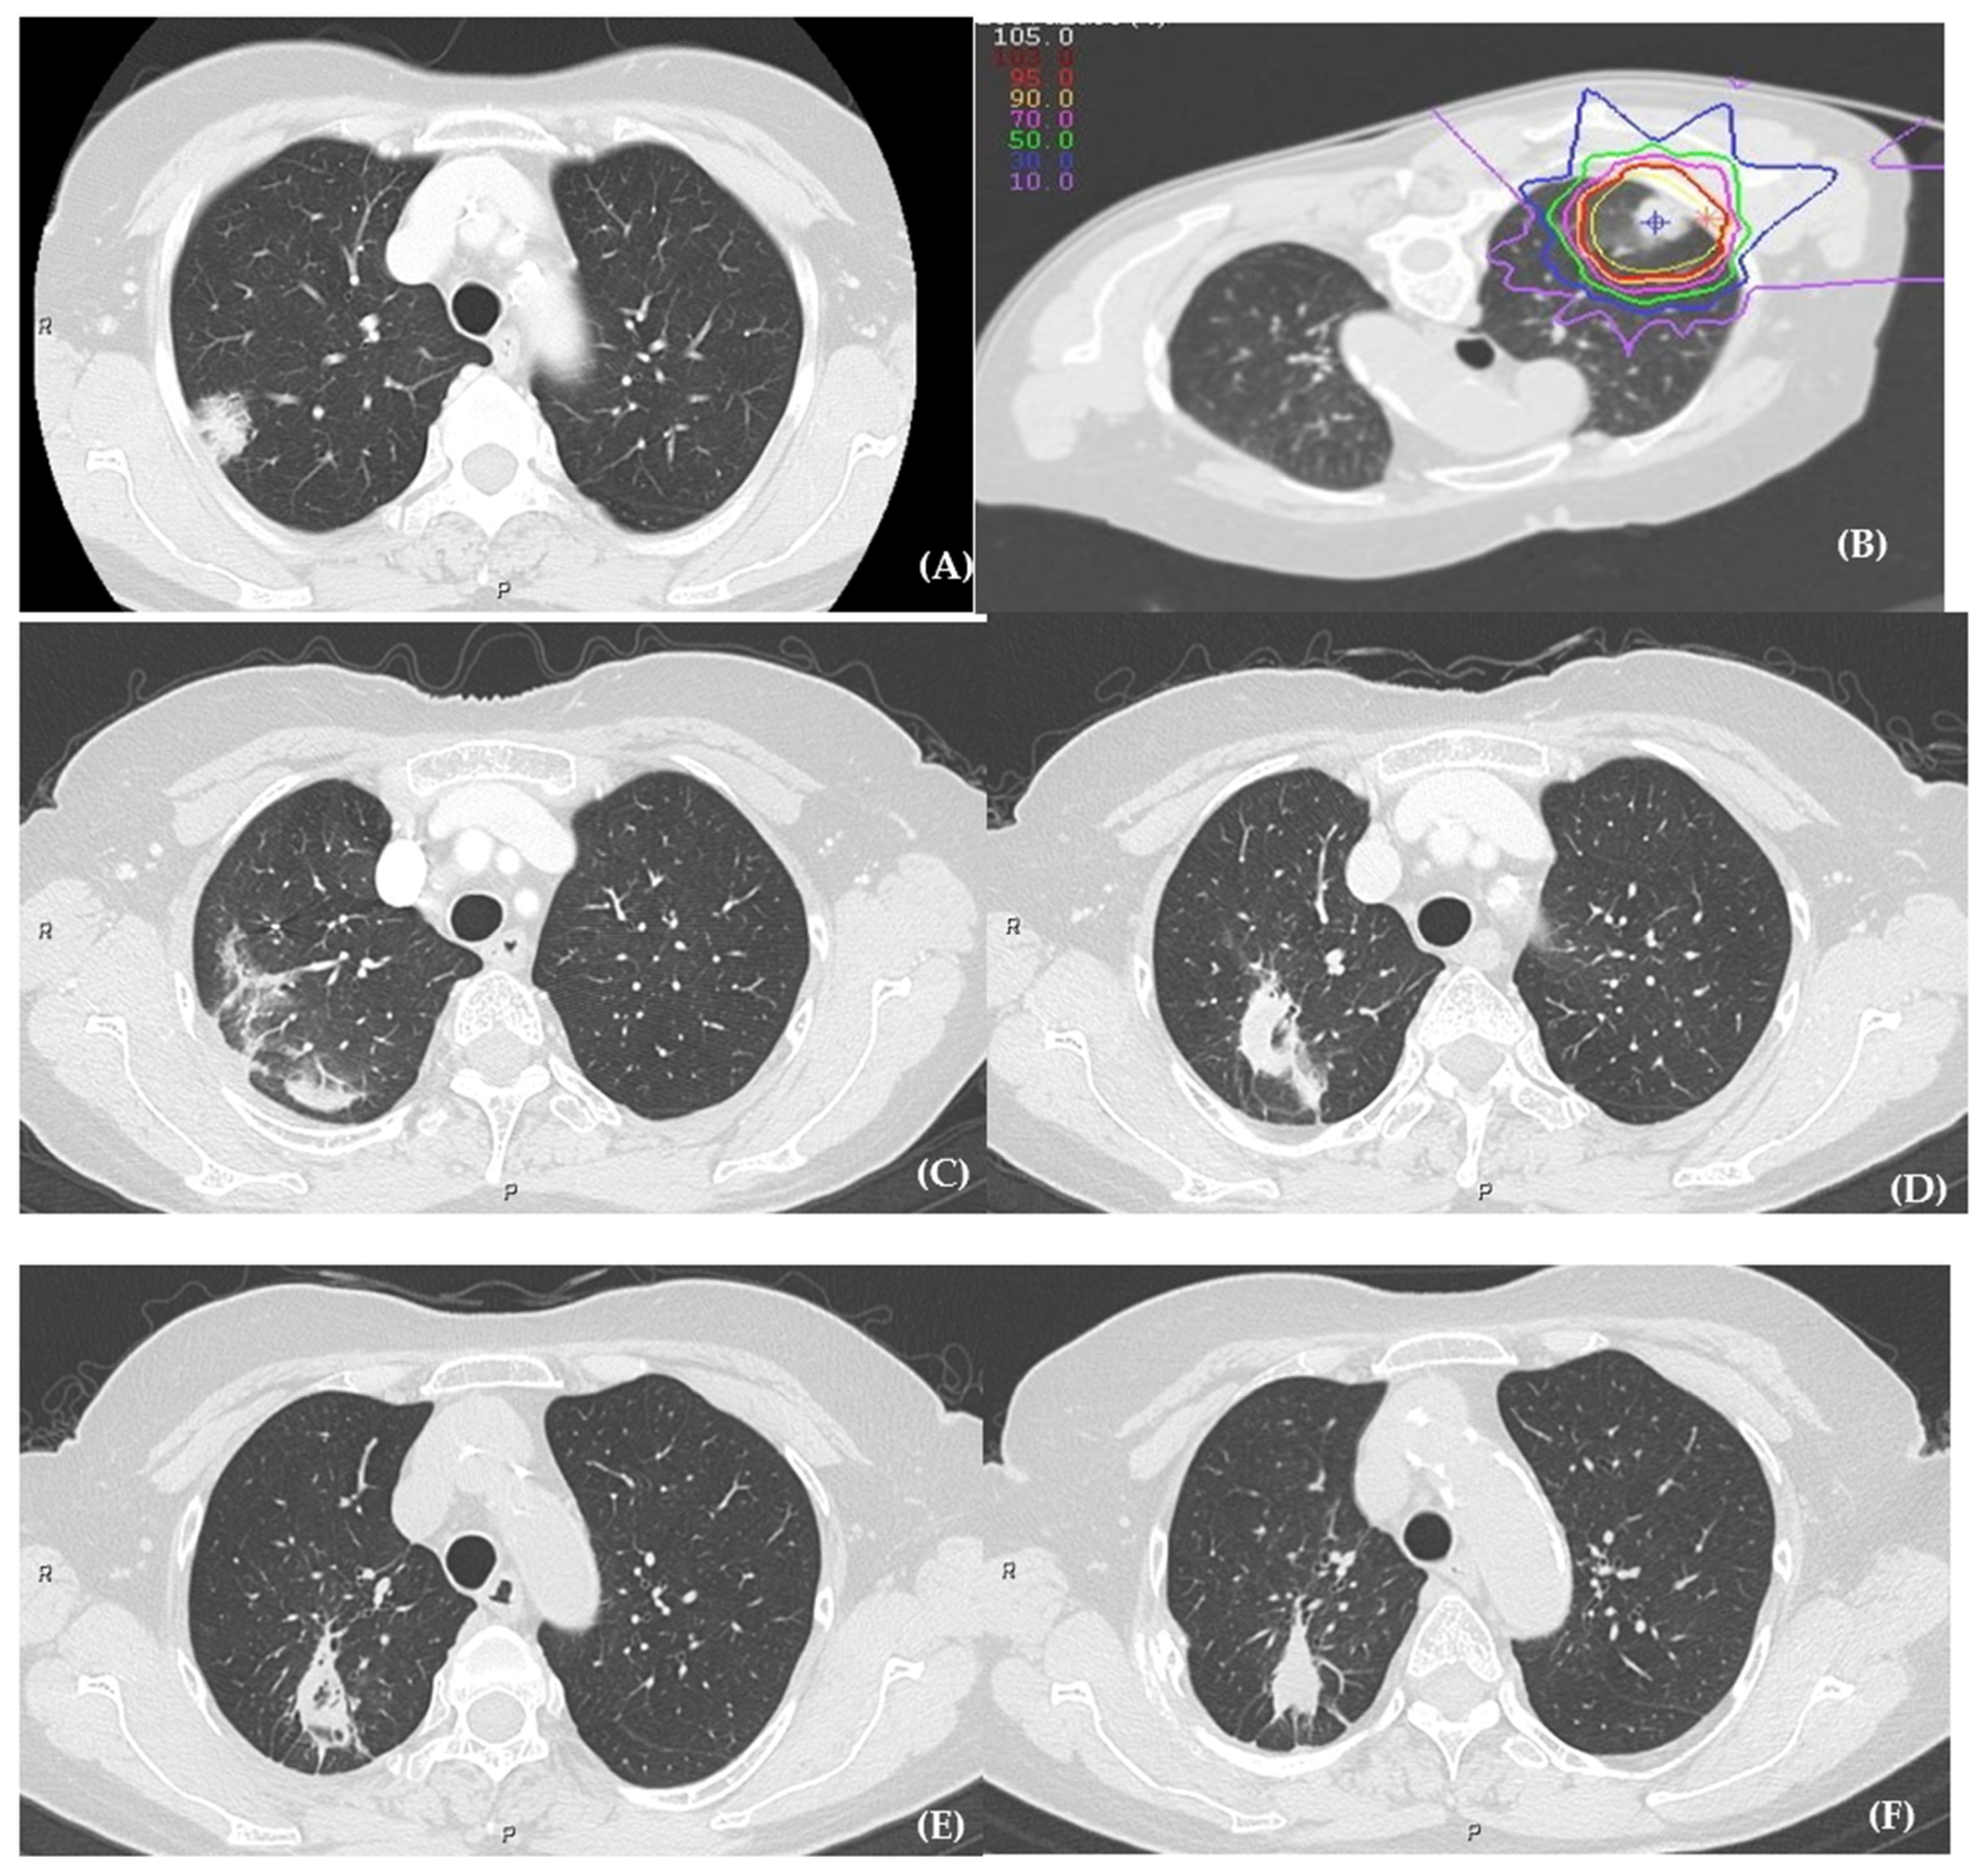

2.3. Carbon-Ion Radiotherapy

- Yamamoto, N.; Miyamoto, T.; Nakajima, M.; Karube, M.; Hayashi, K.; Tsuji, H.; Tsujii, H.; Kamada, T.; Fujisawa, T. A Dose Escalation Clinical Trial of Single-Fraction Carbon Ion Radiotherapy for Peripheral Stage I Non–Small Cell Lung Cancer. J. Thorac. Oncol. 2017, 12, 673–680. [Google Scholar] [CrossRef] [PubMed] [Green Version]

- Ono, T.; Yamamoto, N.; Nomoto, A.; Nakajima, M.; Isozaki, Y.; Kasuya, G.; Ishikawa, H.; Nemoto, K.; Tsuji, H. Long Term Results of Single-Fraction Carbon-Ion Radiotherapy for Non-Small Cell Lung Cancer. Cancers 2020, 13, 112. [Google Scholar] [CrossRef] [PubMed]